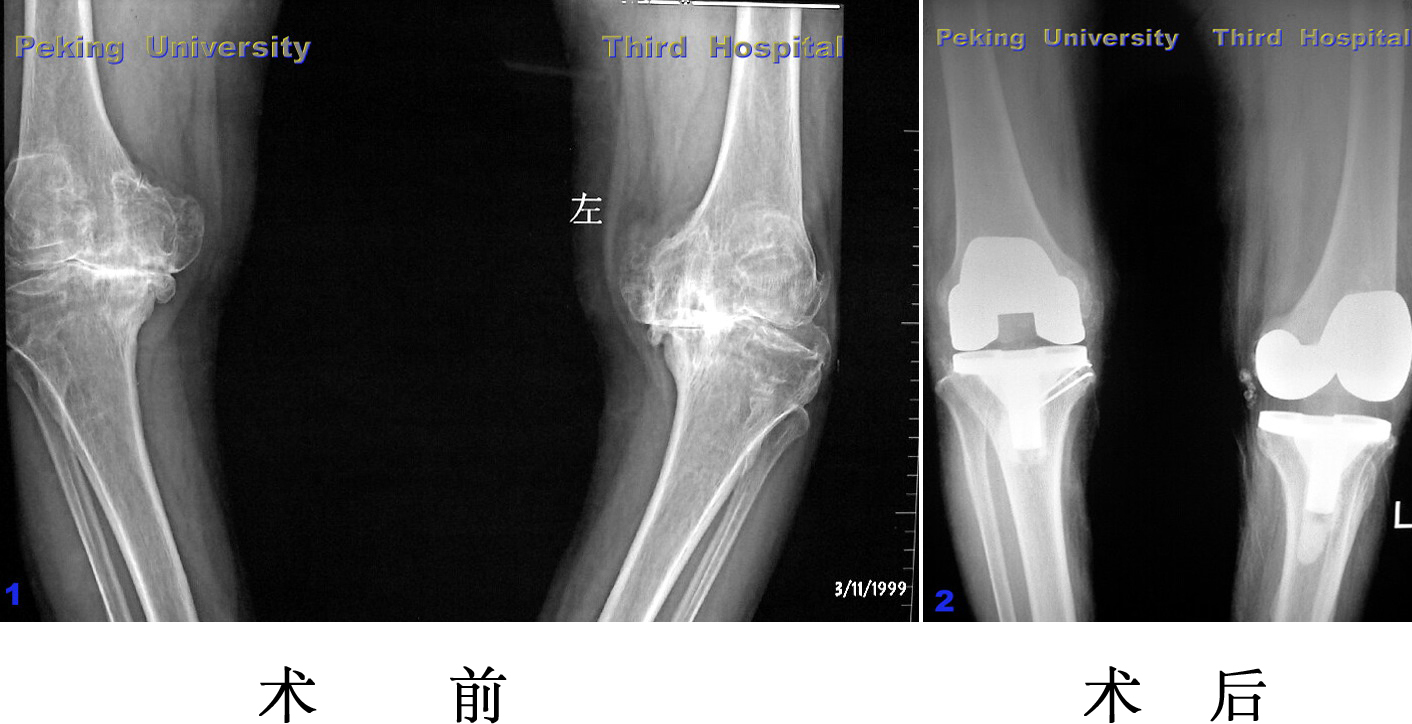

感染翻修

膝关节骨巨细胞瘤接受肿瘤假体置换,术后半年发现感染,

再手术取出假体,三月后感染控制,再次植入假体